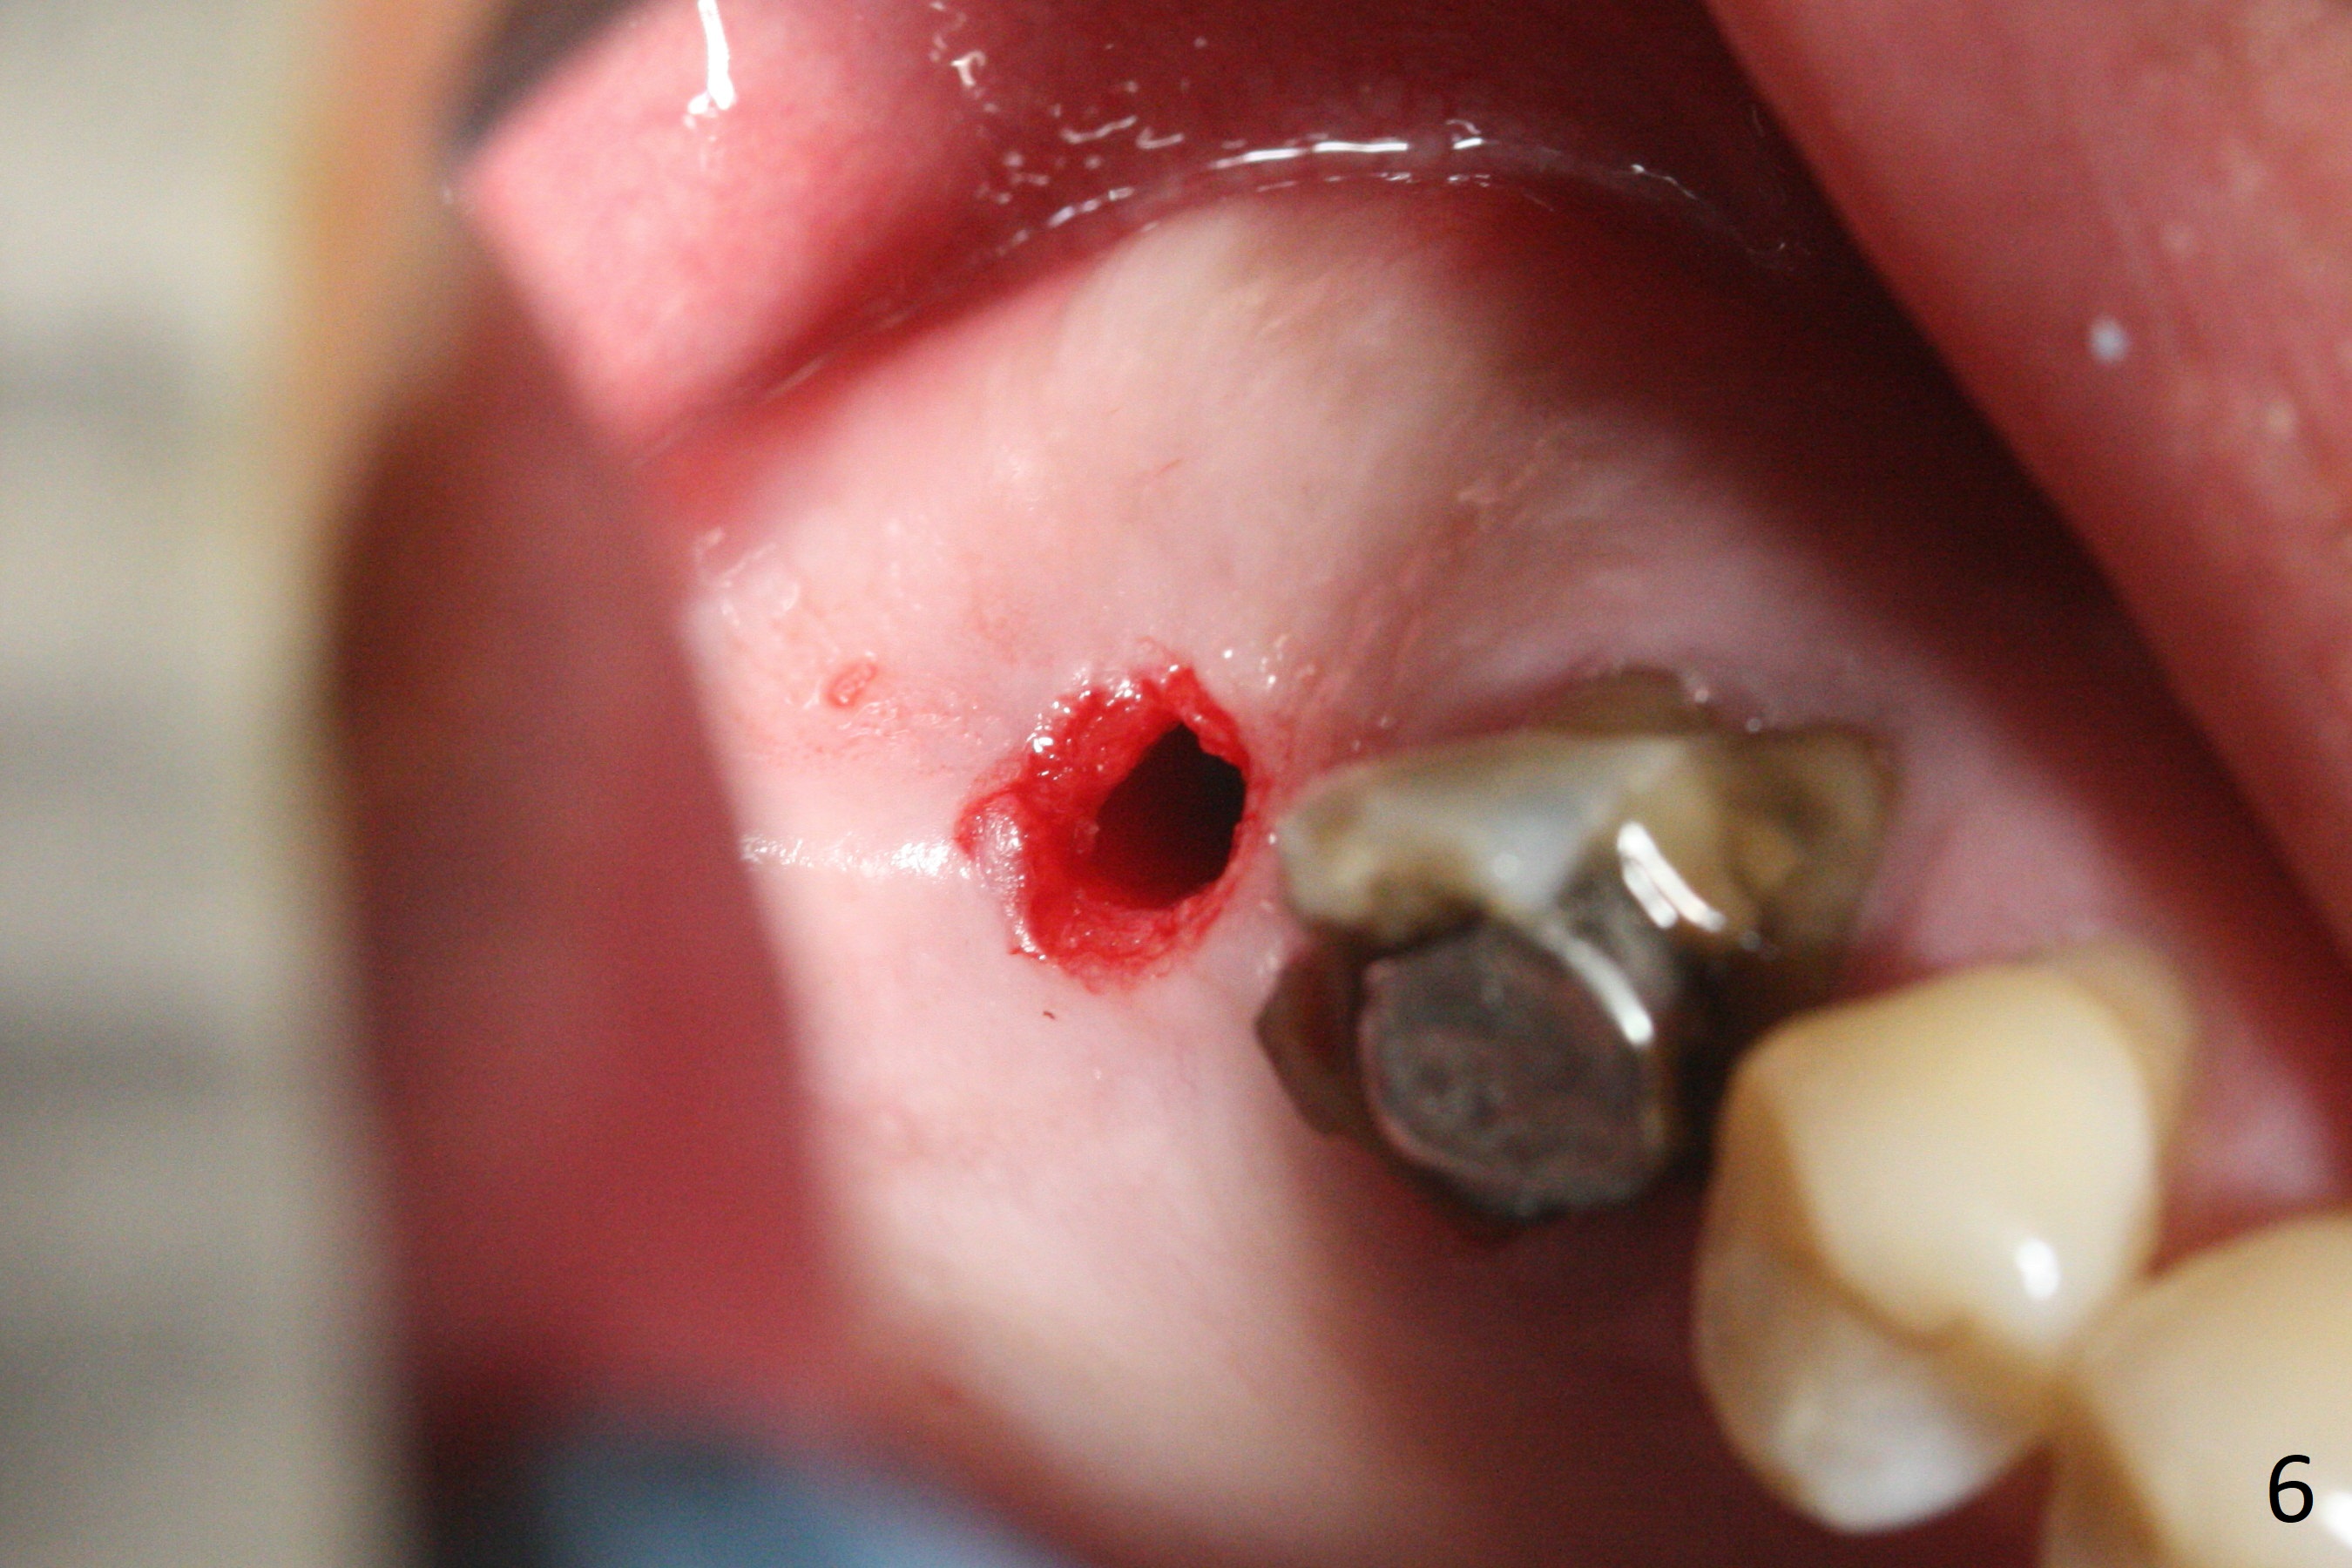

Since the ridge is wide at the site of #2, Magic Split is used for access (flapless) and bone expansion. The bone is so soft that there is no resistance until 4.3 mm Magic Expander is used for 9 mm (Fig.6). A 5 mm tap drill is stable (Fig.1), so are a 5.5x9 mm dummy implant (Fig.2) and a 6x9 mm IBS implant (Fig.3 (<: sinus lift)). In fact the distal thread is still supracrestal (Fig.4 (BW)). After additional 2 mm placement, the distal thread is subcrestal (Fig.5); the mesial margin of a 6.5x4(4) mm abutment is subgingival. A longer cuff (5 mm instead of 4 mm) is more favorable for future restoration. At present the abutment (Fig.7) as well as the tooth #3 with rugged surfaces is used to hold periodontal dressing in place. The abutment margin is completely subgingival 3 months postop (Fig.8 (white dashed line: gingival margin)). It appears that the implant is placed ~ 1 mm deeper than ideal (Fig.9). Diode laser is used for gingivectomy prior to impression. The abutment screw becomes loose 2 months post cementation. After retightening, occlusal equilibrium is conducted with 3 layers of articulating paper. Night guard is provided. The crown/abutment dislodges 1 year 2 months later. Since the gingiva is erythematous, a 6x7 mm healing abutment is placed (Fig.10). The implant seems to have been placed too deep and palatal. It appears that an abutment driver should be buried to prevent the screw re-loosening. Guided surgery should have been done.